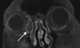

Dacryocystitis

Dacryocystitis is an infection of the lacrimal sac, secondary to obstruction of the nasolacrimal duct at the junction of lacrimal sac. The term derives from the Greek dákryon (tear), cysta (sac), and -itis (inflammation). [Source: Wikipedia ]